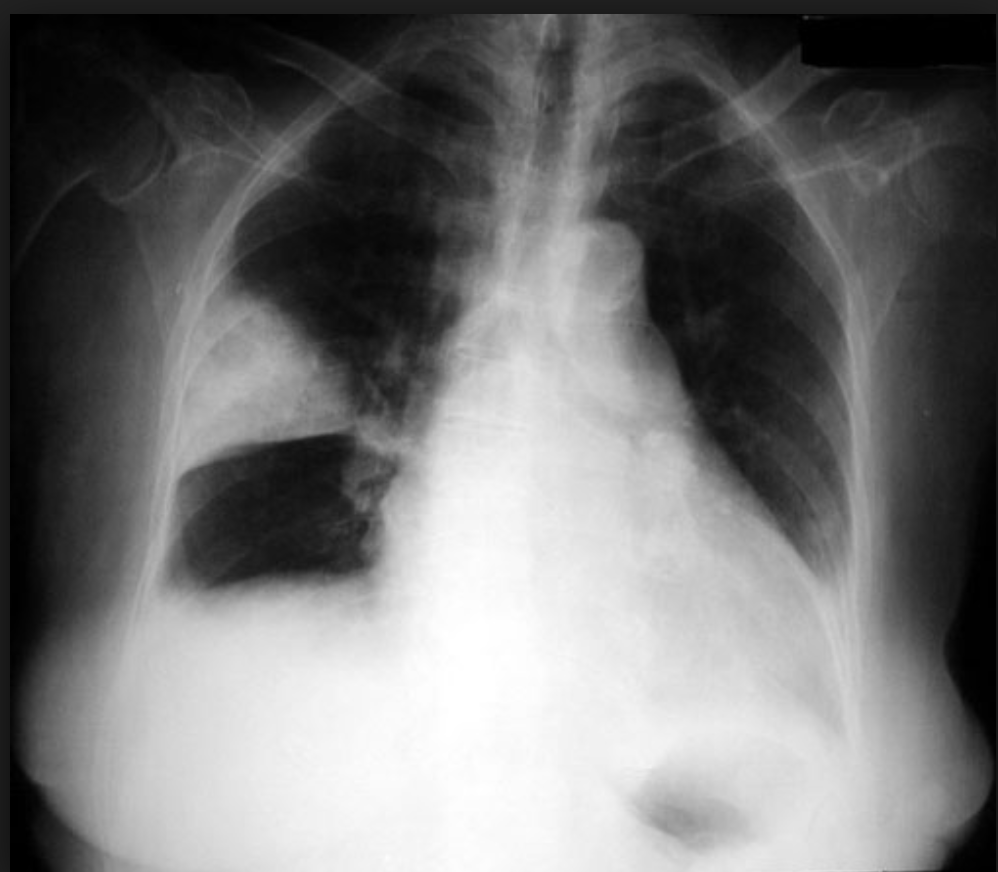

A patient presents to the emergency department with breathlessness following chest trauma. The chest X-ray is shown in the image below. What is the most appropriate next step in management?

Explanation: ***Plan for insertion of a chest tube*** - In **traumatic hemothorax** or **large pneumothorax** following chest trauma, **chest tube insertion** is the definitive emergency management to drain blood/air and prevent cardiovascular compromise. - **Tube thoracostomy** allows continuous drainage, lung re-expansion, and monitoring of ongoing bleeding, which is crucial in trauma patients. *Order for HRCT Scan* - **HRCT** is not the immediate next step in **emergency trauma** management when chest X-ray already shows significant pleural collection. - Delays definitive treatment and is inappropriate when **hemodynamic instability** or **respiratory compromise** may be present. *Thoracocentesis* - **Needle thoracocentesis** is inadequate for **traumatic hemothorax** as it cannot provide continuous drainage or handle large volumes of blood. - Reserved for **diagnostic purposes** or small pleural effusions, not for emergency trauma management with significant collections. *Observe and monitor* - **Conservative management** is inappropriate for significant **post-traumatic pleural collections** that can cause respiratory compromise. - Risk of **tension pneumothorax**, **hemodynamic instability**, or **delayed complications** makes observation insufficient in trauma patients.